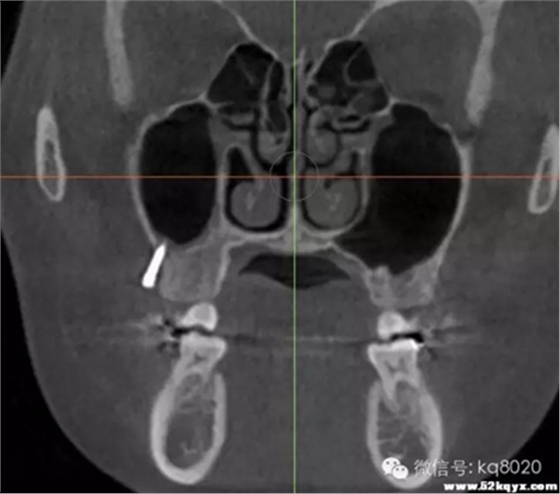

顴牙槽嵴(成人多在67之間,未成年多在56之間或6上方,根據(jù)CT確定)

危險(xiǎn)因素:此處植入容易穿破上頜竇底,植入角度需注意;骨質(zhì)較為堅(jiān)硬,支抗釘易折斷

植入位置和角度:在不滑脫的基礎(chǔ)上越平行于骨面越安全。要根據(jù)顴牙槽嵴的斜度決定植入角度,為避免滑脫,

可先垂直于骨面植入,在調(diào)整方向斜向上,一般植入角度向牙合面旋轉(zhuǎn)60°-70°

大?。河捎诖颂幑琴|(zhì)堅(jiān)硬,宜用10×2.0mm,且支抗釘尖端應(yīng)有切削頭設(shè)計(jì),以切削骨碎屑,利于植入腭側(cè)牙根之間